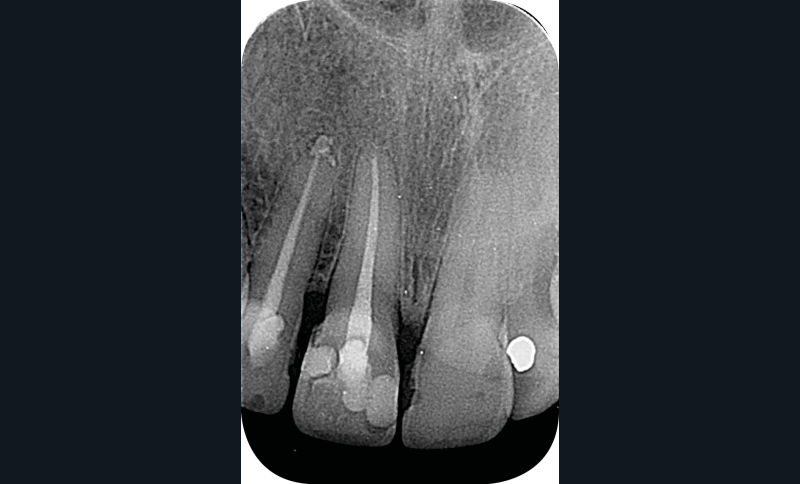

– la nécrose, qui va donner une coloration plutôt brune [3] (fig. 1, 2) ;

– le trauma, qui va donner une couleur plutôt rouge [4] (fig. 3) ;